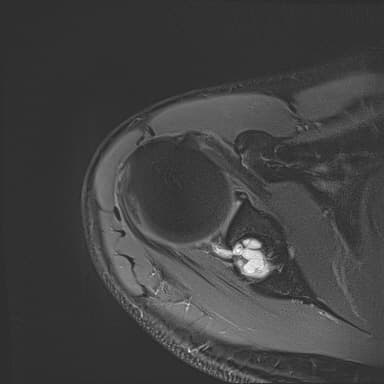

어깨 mri 좀 봐주세요 물혹있다고 하는데 수술해야 하나요?

하도 안 나아서 우측 견관절도 mri 촬영을 했는데 물혹이 있네요

• 3번 째 사진